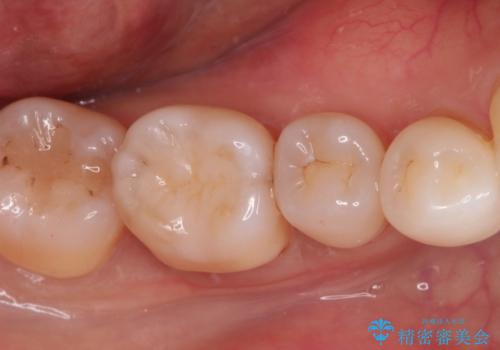

見た目もよく強度の高いものでの修復を希望されましたのでセラミックインレーにて修復しました。

当院でのセラミックインレーは歯とのつなぎ目を拡大鏡で確認して精度高く仕上げるため、むし歯のリスクを限りなく少なくできるよう治療します。